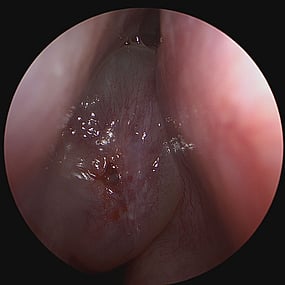

Sino-Nasal Polyps

Sino-Nasal Polyps are non-cancerous growths that develop in the lining of the nose or sinuses. They can obstruct the nasal passages and sinuses, leading to symptoms similar to chronic sinusitis such as nasal congestion, facial pressure, and reduced sense of smell.